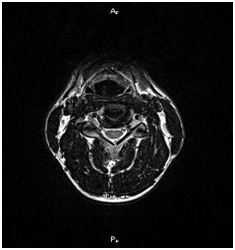

MRI lehetővé teszi, hogy megjelenítsék morfológiai változások: a csigolyatestek, porckorongok, gerincvelő, dura térben, az ideg gyökerek környező paravertebralis lágyrész, érrendszeri szerkezetek, amelyek a kutatási területen.

A szklerózis multiplex. Foci demielinálódás a gerincvelőben.

T1VI T2VI T1 (kontraszt)

gerinc kavernoma

Epidurális vérömleny a nyaki gerinc

Rheumatoid arthritis atlanto-axiális közös.